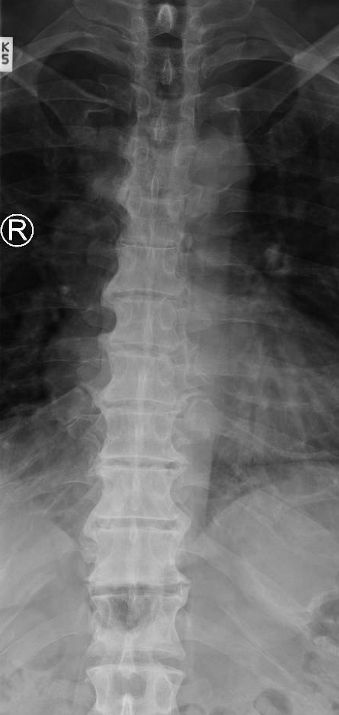

Calcification of anterior and posterior longitudinal ligaments in DISH will lead to appearance of _____ on radiography